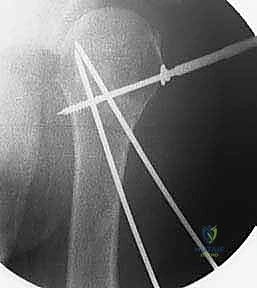

4. إدخال الأسلاك المعدنية (K-wires)

بمجرد أن يصبح الكسر في الوضع المثالي، يتم إدخال أسلاك كيرشنر (Kirschner wires) الدقيقة عبر الجلد مباشرة إلى العظم. يتم توجيه هذه الأسلاك بزوايا هندسية مدروسة لضمان أقصى درجات الثبات. عادة ما يتم استخدام 2 إلى 4 أسلاك.

5. التحقق من الثبات وقص الأسلاك

بعد وضع الأسلاك، يتم تحريك الكتف بحذر للتأكد من ثبات الكسر التام. بعد ذلك، تُقص نهايات الأسلاك وتُترك بارزة قليلاً فوق الجلد (أو تُدفن تحت الجلد مباشرة) لتسهيل إزالتها لاحقاً.

6. التقييم النهائي والإغلاق

تُؤخذ صور شعاعية نهائية لتوثيق نجاح العملية، وتُغطى مواقع دخول الأسلاك بضمادات معقمة.

صور إضافية من داخل غرفة العمليات توضح دقة الإجراء: